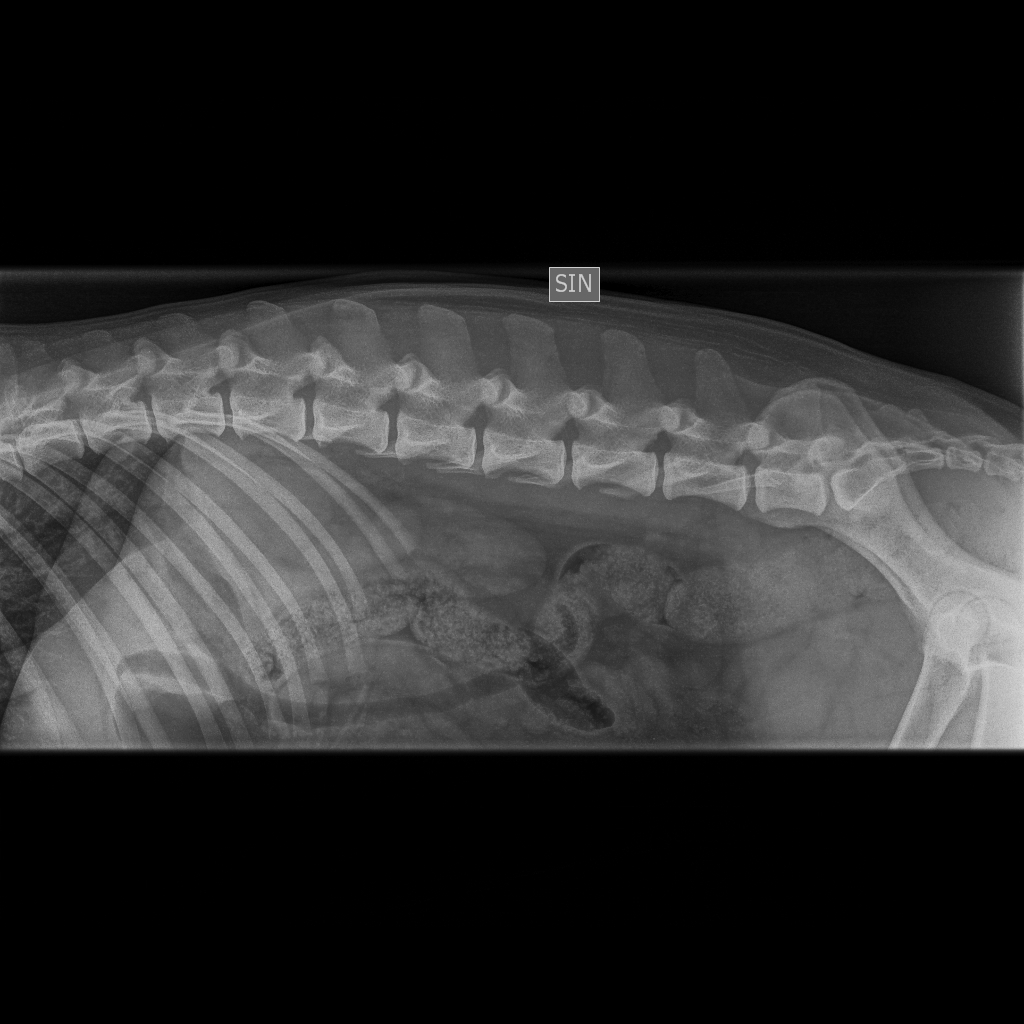

Viralliset selkäkuvat |

Välimuotoinen lanne-ristinikama: LTV0 (normaali) |

Muu luusto *) | Selkäranka, polvet ja olkapäät OK | Selkäranka ja olkapäät OK, polvet 0/0 | - | Selkäranka, polvet ja olkapäät OK | Selkäranka ja olkapäät OK, polvet 0/0 |

*) 6 koiran (muut paitsi Pikimusta ja Parfyymi) luustokuvaukset tehtiin 19.3.10 ell Kari Ventelän toimesta.

Kuvatuissa nivelissä ja selkärangassa ei havaittu muutoksia.